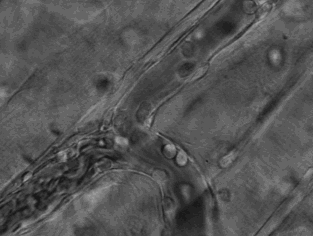

3.這張動(dòng)圖顯示的是嗜酸性粒細(xì)胞在趨化作用的“感知”下逐漸聚集到一只秀麗隱桿線蟲周圍并對(duì)它進(jìn)行攻擊的過程。有“成千上萬”的嗜酸粒細(xì)胞圍聚在線蟲周圍,就像一群螞蟻,善打“包圍戰(zhàn)”。